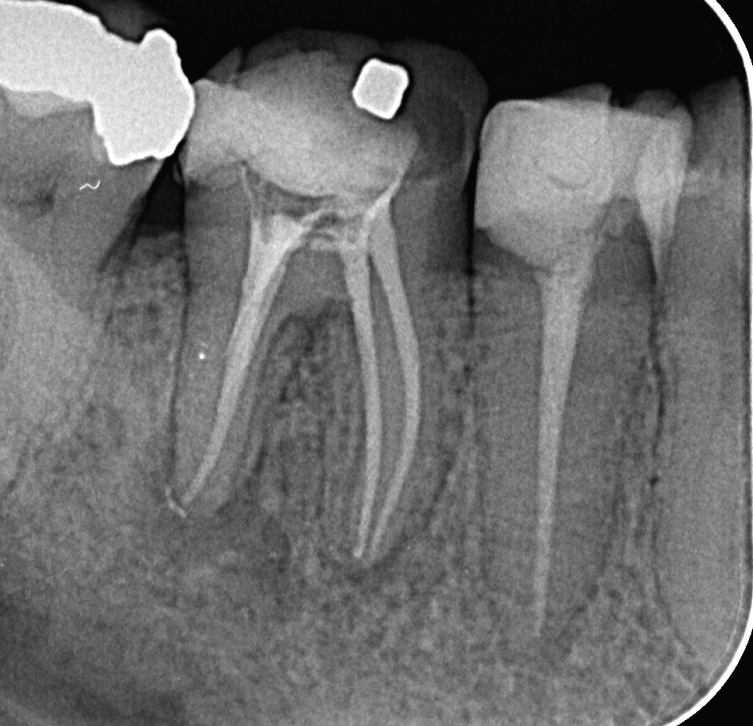

Here on the picture below you can see inadequate endodontic treatment and infection around the tooth (dark area around the roots).

And on the next picture you can see regular and well maintained endodontic treatment and there`s no infection. This tooth can last for life.